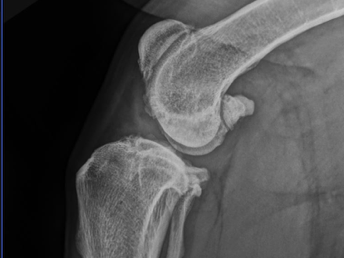

Osteoarthritis

Back to Surgery Information Pet Owner Information Osteoarthritis (OA) What is osteoarthritis? Osteoarthritis is defined as aberrant degradation and attempts at repair of articular cartilage (the cartilage that lines joint surfaces). This is characterised by loss of...